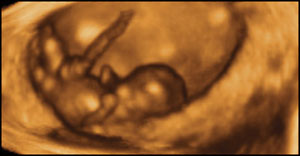

Eight weeks gestation, 40mm from crown to rump.

1 of 10

At eight weeks gestation, this foetus is able to kick and straighten his legs, turn them round and move his arms up and down.